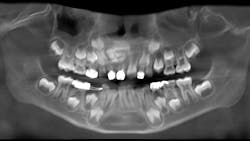

A panoramic film (figure 1) taken by the general dentist revealed a large radiodense area in the region apical to teeth D and E. The patient was referred to an oral and maxillofacial surgeon who obtained a CBCT scan (figure 2).

Clinical and radiographic assessment revealed retained primary teeth D and E, and buccal cortical expansion over the apices of these teeth. A cone beam CT scan revealed a well circumscribed, mixed radiodensity overlying the apices of the primary teeth, adjacent permanent teeth nos. 7 and 8 displaced in a caudal direction, and cortical expansion.